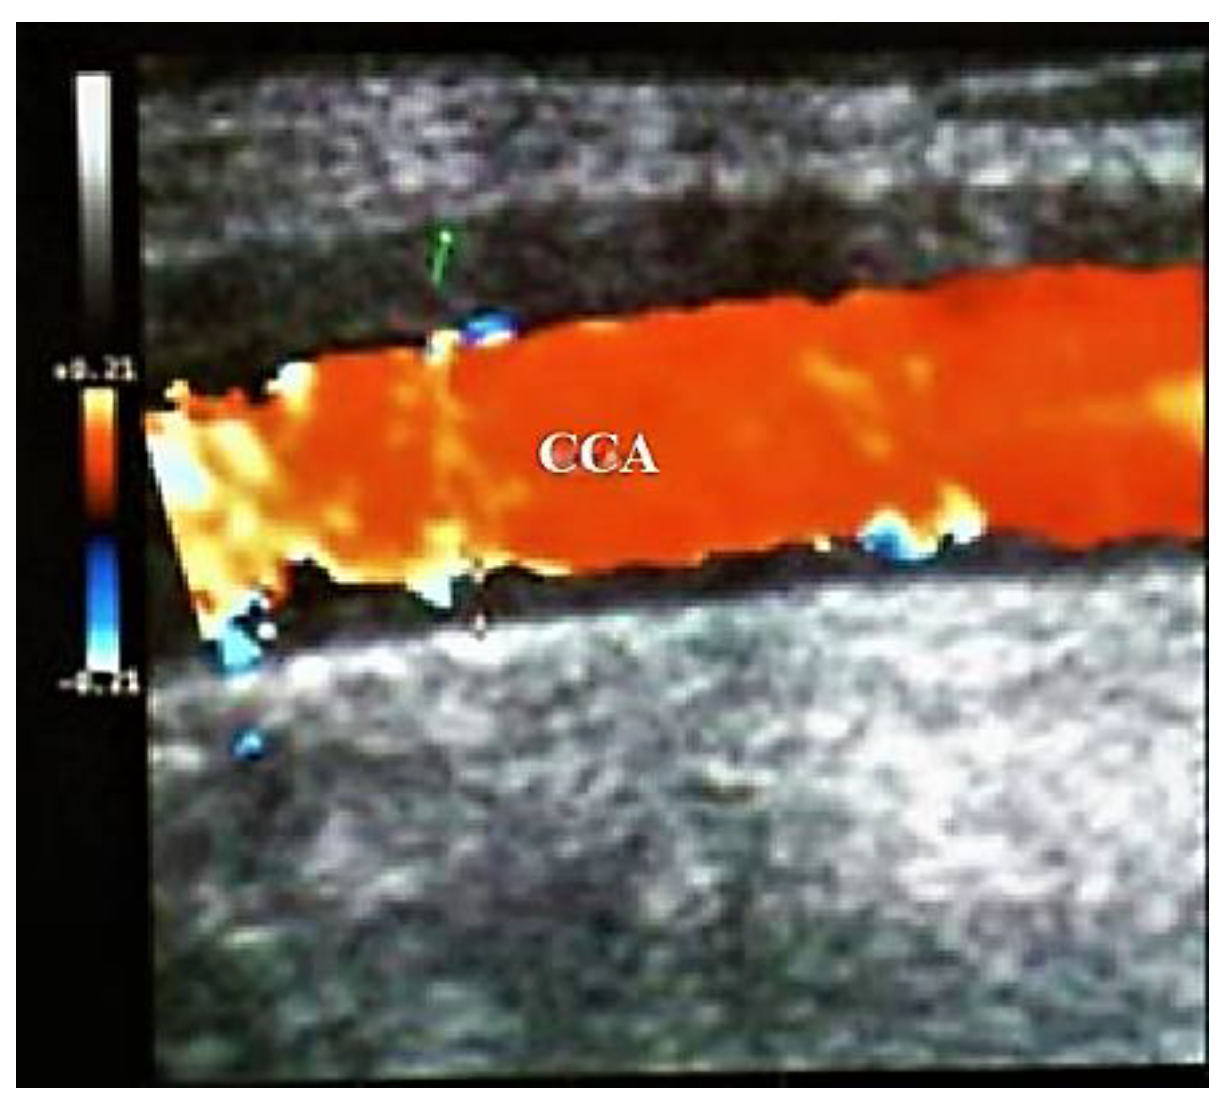

- Large size arteries: the common carotid arteries (CCAs), the ECAs, the internal carotid arteries (ICA’s), the vertebral, the subclavian, and the axillary arteries,

- US image of wall thickening (“halo”) is brighter in Takayasu arteritis than in GCA, because the patient with GCA has a larger mural edema than in Takayasu arteritis (GCA being a more acute disease than Takayasu arteritis) [30].